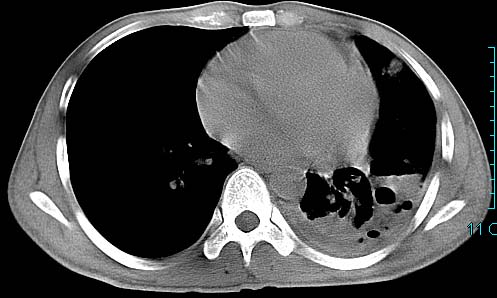

以下是引用ctkz987在2006-3-28 13:04:00的发言:[br]左侧胸腔积液穿刺后多发气液平(多房性),结合临床有高热不除外合并感染。

以下是引用qian在2006-3-28 14:32:00的发言:[br]左肺下叶大片状阴影,密度不均,见有条片影和空洞及气液平,少量胸腔积液伴有胸膜增厚,从图像看积液密度比水的密度高,结合病史,考虑左下肺化脓性炎症伴有脓胸。

以下是引用wawaquan在2006-3-28 22:25:00的发言:[br]左上肺舌段多发斑片影。结合“男24y咳嗽咳痰气促伴高热(38.5--39.5)20多天”及穿刺史,[br]考虑1 左下肺化脓性炎症;2脓胸。

以下是引用乡医在2006-3-28 18:37:00的发言:[br]左侧多发液气平面结合患者男24y咳嗽咳痰气促伴高热(38.5--39.5)20多天,查胸水:ldh239.3,总蛋白59.19,tb-ab阴性,利凡它试验+,红c2.7*109,白c1.08*109,分类淋巴92%分叶8%,考虑1脓胸2肺隔离征感染